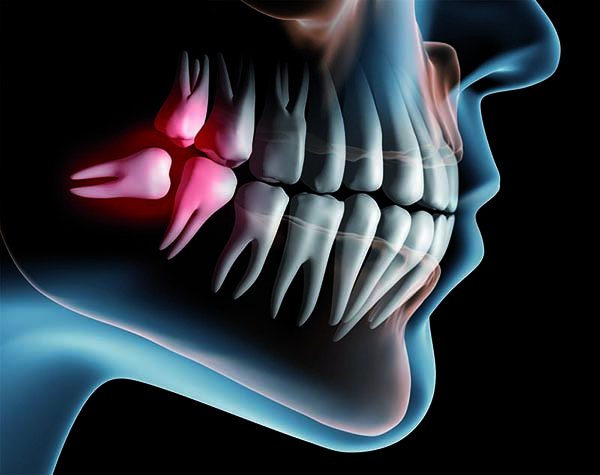

Bei den meisten Menschen reicht der Platz im Kiefer für diese Weisheitszähne nicht aus, so dass sie sich häufig nicht korrekt in die Zahnreihe einordnen können. Die Zähne bleiben dann ganz oder teilweise im Kiefer eingeschlossen, man bezeichnet diesen Zustand als "retiniert".

• Die Zahnkrone ist vom Knochen durch einen kleinen Spaltraum abgegrenzt. In diesem Schlupfwinkel entstehen häufig (bei bis zu 50 %) Infektionen, die in einzelnen Fällen bis zu schweren Abszessen fortschreiten können.

• Durch die Krone des Weisheitszahns bzw. das Umgebungsgewebe können die Backenzähne geschädigt und Teile der Wurzel regelrecht aufgelöst werden. In gleicher Weise kann das Zahnbett des benachbarten Backenzahnes geschädigt werden.